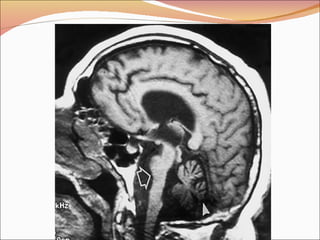

Organización externa El  cerebro humano de un adulto  pesa aproximadamente 1400 gr y tiene un volumen entre 1350 y 1500 cc. Presenta  circunvoluciones  que permiten que una mayor superficie cerebral esté contenida en el cráneo